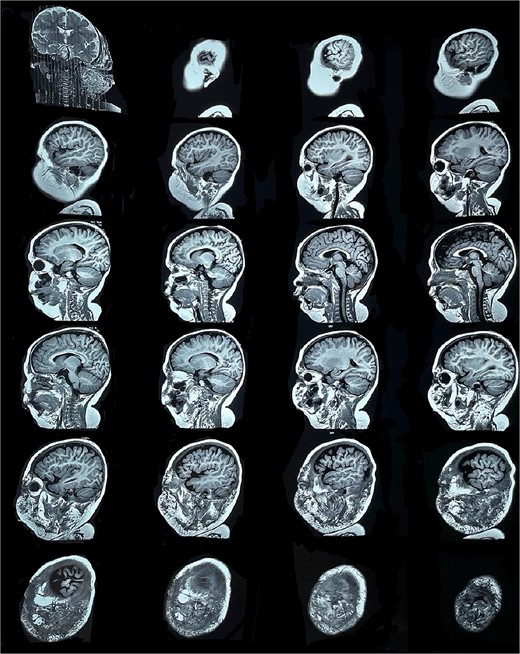

Six months later, the patient developed fever and severe edema that prevented the opening of the left eye, resulting in decreased overall tolerance. Laboratory results showed leukocytosis, severe thrombocytopenia (platelet count of 6000), and a positive C-reactive protein test. Physical examination revealed an irritable and lethargic patient with a 15 × 20 cm red mass with irregular borders (Fig. 1). An angioresonance was performed, revealing a hemangioma on the left hemiface that infiltrates muscle planes, the left parotid gland, and the auricular pavilion, ~10.7 × 6.6 × 13 cm in size, with possible vascularization from branches of the external carotid artery (Figs 2 and 3), leading to the diagnosis of KMP.

Angioresonance with evidence of a hemangioma on left hemiphase (cross-sectional).

Angioresonance with evidence of a hemangioma on left hemiphase (coronal plane).